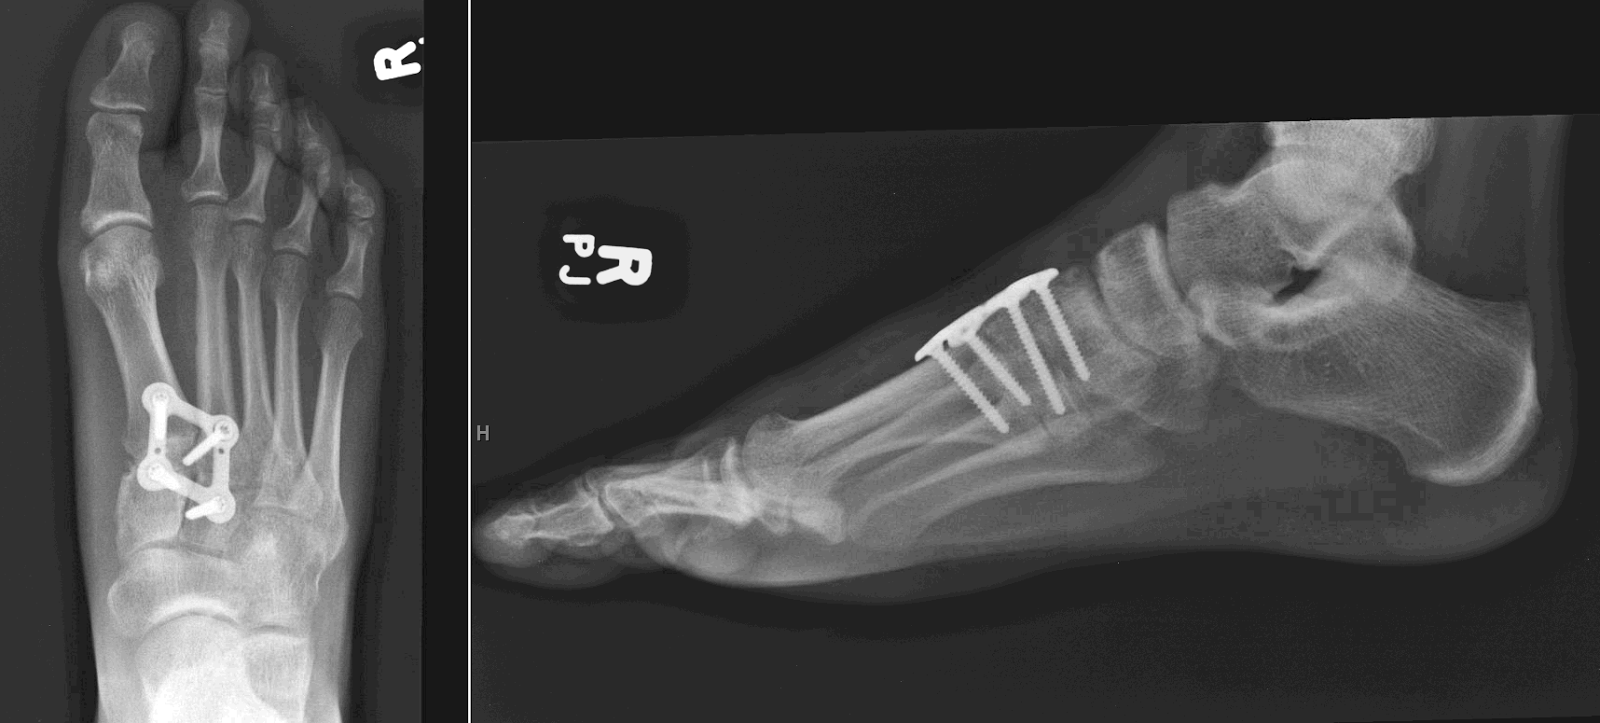

(A and B) The weight bearing AP view of bilateral feet. The arrow shows

(A and B) The weight bearing AP view of bilateral feet. The arrow shows What Is Bilateral Foot Surgery orthopedics foot and ankle surgery. Bunion surgery is done to reduce the pain and correct the deformity. It is important to note. bunion surgery (bunionectomy) is surgery to remove a bunion from the joint where your big toe meets your foot. the answer is yes, most patients who have bunions on both feet can have what is. What Is Bilateral Foot Surgery.